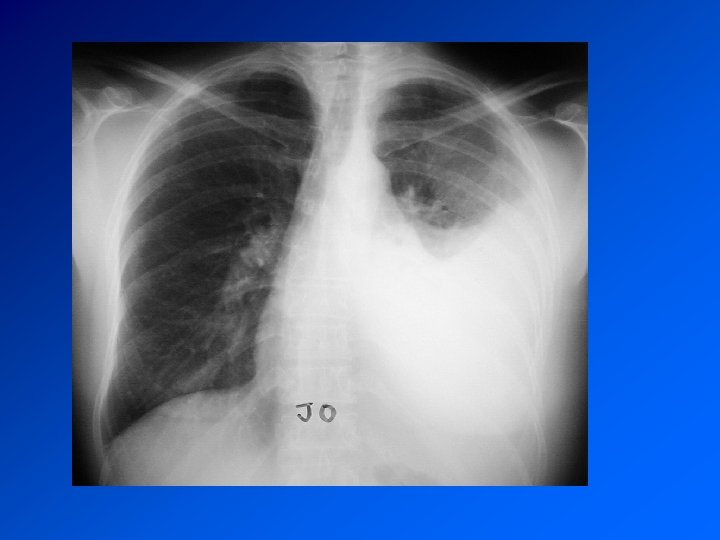

DIAGNOSTIC CDD : Dyspnée, Douleur Autres signes en fonction de l’étiologie Examen : syndrome pleural : matité, abolition de la transmissions des vibrations vocales, abolition du murmure vésiculaire Radio : opacité dense, limitée par une ligne concave en haut et en dedans : la ligne de Damoiseau Bilan biologique : en fonction de l’étiologie

Enquête diagnostique Histoire de la maladie : recherche une maladie déjà connue, une exposition à un toxique professionnel, la prise de médicaments Examen clinique retrouve le syndrome pleural. Recherche de signes d’autres maladies associée Radio de thorax : fait le diagnostic TDM Thorax : précise les images Ponction pleurale oriente en fonction de la cytologie

PATHOLOGIES NEOPLASIQUES Pleurésie néoplasiques métastatiques : Cancer primitif : poumon, sein, prostate, digestif (estomac, colon) Révélateur ou compliquant la maladie Traitement : du cancer primitif De la pleurésie : évacuation et TALCAGE PLEURAL

Mésothéliome pleural Cancer primitif de la plèvre Principal facteur de risque (retrouvé dans > 80% des méso): exposition à l’AMIANTE CDD : AEG douleur, syndrome pleural. Surveillance d’un sujet exposé Radio : pleurésie. Epaississement tumoral nodulaire de la plèvre. Extension extrathoracique rare mais possible Evolution défavorable. Survie moyenne 9 à 12 mois. Traitement décevant : chimiothérapie. Radiothérapie sur orifices biopsies et drainage Symphise pleurale